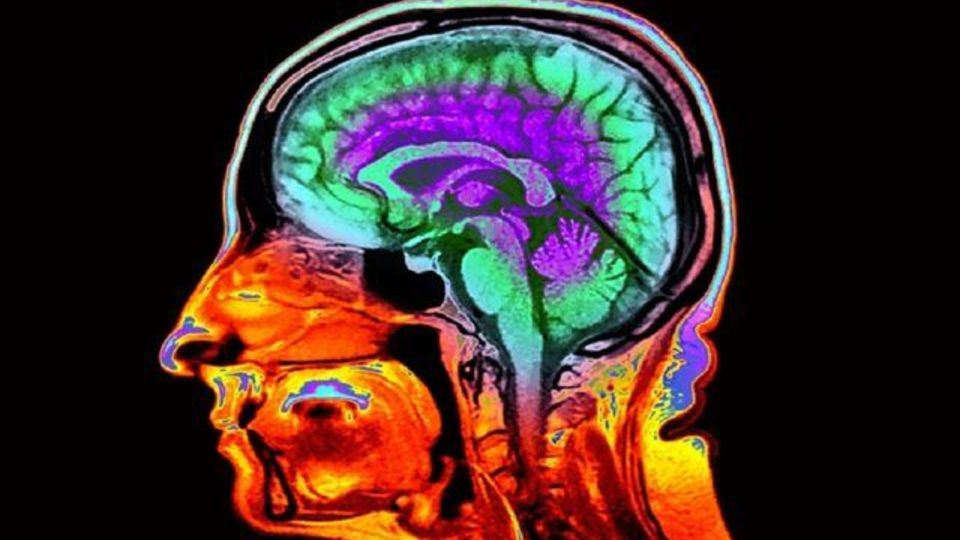

به گزارش ایسنا، مطالعهای که بیش از ۵۰ هزار اسکن مغزی را بررسی کرده، نشان داده که ویژگیهای مشخصی در تصاویر رایج مغزی میتوانند سرعت پیری یک فرد را آشکار کنند.

به نقل از نیچر، از جمله این ویژگیهای کلیدی، ضخامت قشر مغز که ناحیهای است که مسئول زبان و تفکر است و حجم ماده خاکستری آن است. این ویژگیها و موارد دیگر میتوانند پیشبینی کنند که توانایی ذهنی و حافظهی فرد با افزایش سن چقدر سریع افت میکند، و همچنین میزان خطر ابتلا به بیماری، ناتوانی جسمی یا حتی مرگ را نشان میدهد.

برای ساخت ساعتی دقیقتر، اتان ویتمن، پژوهشگر پیری مغز در دانشگاه دوک در کارولینای شمالی، با همکارانش سراغ یک مطالعهی خاص رفتند: بررسی بیش از ۱۰۰۰ نفر که بین ماههای آوریل ۱۹۷۲ تا مارس ۱۹۷۳ در دونیدین نیوزیلند متولد شدهاند و از بدو تولد بهطور منظم مورد مطالعه قرار گرفتهاند. در تازهترین بررسیها، از مغز این شرکتکنندگان تصویربرداری MRI انجام شد.

گروه ویتمن دادههای بهدستآمده از ۸۶۰ اسکن مغزی را وارد الگوریتم خود کرد تا ارتباط بین این دادهها و مفهومی بهنام «سرعت پیری» را بررسی کند. مفهومی که شامل کاهش عملکردهای قلبیعروقی، سوختوساز، ایمنی و دیگر شاخصهای زیستی در این افراد است.

نتیجهی کار، ساخت ساعتی زیستی جدید بود: امتیاز بالاتر در این سنجش با خطر بیشتر بیماریهای مزمن در آینده و مرگ زودرس ارتباط داشت. این یافته نهتنها در نمونهی دونیدین، بلکه در تحلیل ۴۲ هزار و ۵۸۳ اسکن از بانک اطلاعاتی زیستی بریتانیا و ۱,۷۳۷ اسکن از ابتکار تصویربرداری بیماری آلزایمر نیز تایید شد.